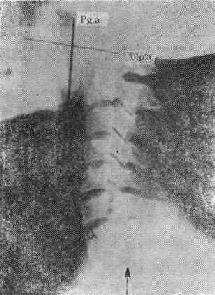

片中示较大的食团卡在喉部

图113-2 片中示较大的食团卡在喉部